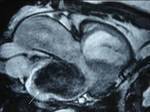

Results: Twenty-two cardiac masses were successfully detected and their characteristics adequately delineated, including eight myxomas, one angiosarcoma, one ventricular lymphoma, one endocardiac metastasis, one epicardiac paraganglioma, and 10 cases of intracardiac thrombi.